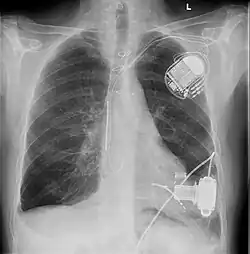

Ein Kunstherz oder künstliches Herz (auch Herzunterstützungssystem, ventricular assist device VAD, und Ventrikuläres Unterstützungssystem genannt) kann in den Körper von Patienten mit unheilbaren Herzerkrankungen (z. B. Herzinsuffizienz) eingesetzt werden, wenn das Herz des Patienten nicht mehr in der Lage ist, den Körperkreislauf ausreichend aufrechtzuerhalten. Deswegen spricht man auch vom Kreislaufunterstützungssystem.

- Diese Art von Kunstherz wird in die linke Herzkammer eingesetzt und pumpt das Blut von dort in die Aorta. Diese Art der Unterstützung des großen Kreislaufs stellt die häufigste Art von Kunstherzen dar.

- Ein RVAD wird in die rechte Herzkammer implantiert und pumpt das Blut in die Pulmonalarterie. Hier wird nur der Lungenkreislauf unterstützt.